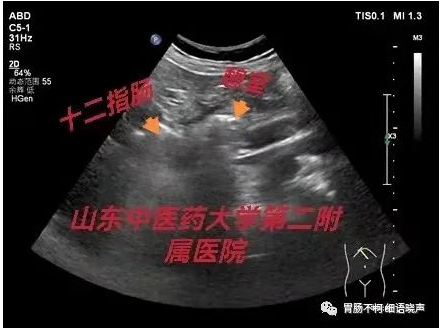

病例三(含气强回声型),十二指肠旁条索状强回声,周边片状高回声不明显,造影剂充盈下的十二指肠短轴切面与憩室的“双腔征”: